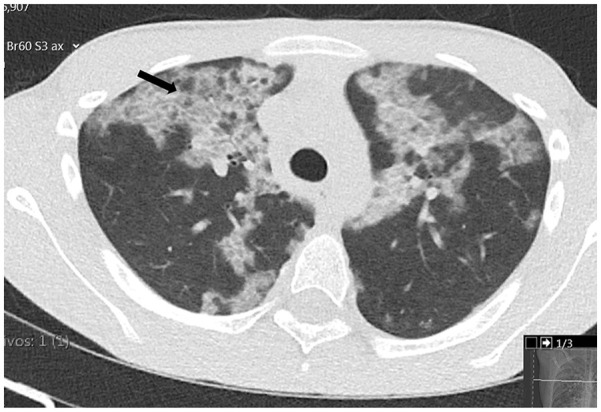

Autoimmune pulmonary alveolar proteinosis (AI-PAP) is a rare condition, especially in children. The clinical presentation ranges from asymptomatic forms to respiratory distress requiring ventilation. We describe the case of a 13-year-old adolescent male who presented to the emergency department with acute pleuritic chest pain not associated with systemic complaints. On examination, he had diminished breath sounds in the lower two thirds of the chest with no other abnormal findings; SpO2 (oxygen saturation) was 98% on room air. Chest radiograph revealed a marked interstitial infiltrate, comparable with the one taken 4 years earlier during an acute illness that was presumptively treated with azithromycin. A computed tomography (CT) scan revealed multiple bilateral areas of ground-glass opacities with areas of crazy paving, involving > 65% of lung parenchyma, suggestive of pulmonary alveolar proteinosis (PAP). Respiratory viral testing, including for coronavirus (SARS-CoV2), was negative. Bronchoalveolar lavage performed in the outpatient setting revealed a milky fluid and positive periodic acid-Schiff staining. Spirometry indicated a mild restrictive pattern (forced vital capacity [FVC] = 77%) and diffusing capacity of the lungs for carbon monoxide (DLCO) showed a moderate decrease at 48.6%. No mutations associated with surfactant dysfunction were found on the genetic panel. Anti-granulocyte macrophage colony-stimulating factor (GM-CSF) antibody testing was strongly positive, raising suspicion for autoimmune PAP. At 20 months of follow-up, the patient remains asymptomatic with a normal spirometry. Although treatment with agents, such as the inhaled form of granulocyte-macrophage colony-stimulating factor (GM-CSF) appears promising for the treatment of symptomatic adult patients, as this patient remains asymptomatic, a conservative approach was taken, and he continues to be monitored in the clinic.